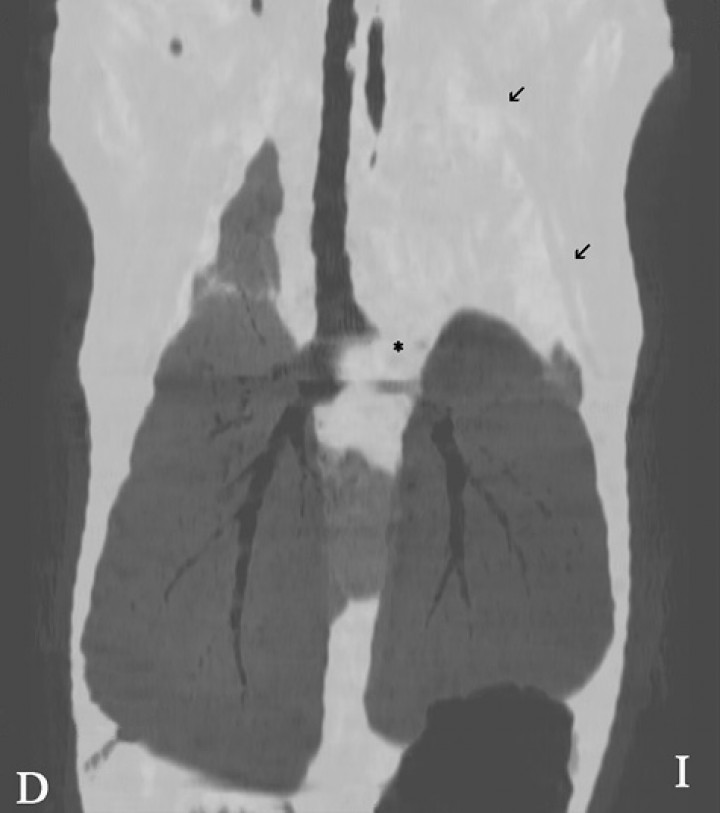

En el caso clínico que se presenta, la TC de la cavidad torácica evidenció una interrupción abrupta del bronquio lobar craneal izquierdo, observándose el lóbulo pulmonar craneal izquierdo (porción craneal y caudal) completamente consolidado con una pequeña zona enfisematosa en su porción más craneal, estando aumentado de tamaño y ocasionando una leve desviación hacia la derecha del mediastino craneal (Fig. 3). Tras la administración de contraste, el lóbulo presentó un realce en anillo con una zona central que no se realzaba con el contraste, siendo compatible con un área de necrosis o la formación de un absceso (Fig. 4).

<p>Imagen de tomografía computarizada (TC) en plano dorsal y reconstrucción en MinP. Se evidencia una interrupción del bronquio lobar craneal izquierdo (asterisco), visualizándose dicho lóbulo pulmonar (flechas negras) consolidado.</p>

Imagen de tomografía computarizada (TC) en plano dorsal y reconstrucción en MinP. Se evidencia una interrupción del bronquio lobar craneal izquierdo (asterisco), visualizándose dicho lóbulo pulmonar (flechas negras) consolidado.

La TC es la herramienta de imagen de elección para el estudio del parénquima pulmonar. En los casos con torsión pulmonar, esta técnica avanzada de diagnóstico por imagen permite la visualización de bronquios con una terminación abrupta, una posición anormal del lóbulo pulmonar y la falta de realce de contraste en todo el lóbulo pulmonar agrandado,[ Davies JA, Snead EC, Phar JW. Tussive syncope in a pug with lung-lobe torsion. Can Vet J, 2011; 52: 656-660. [PubMed] , Seiler G, Schwarz T, Vignoli M, Rodriguez D. Computed tomographic features of lung lobe torsion. Vet Radiol Ultrasound, 2008; 49:504-508. [PubMed] ] siendo signos patognomónicos del proceso. Estos cambios fueron evidenciados en nuestro paciente, junto con una leve efusión pleural, la cual es indicativa de cronicidad del proceso en pacientes con torsión pulmonar.[ Davies JA, Snead EC, Phar JW. Tussive syncope in a pug with lung-lobe torsion. Can Vet J, 2011; 52: 656-660. [PubMed] ]